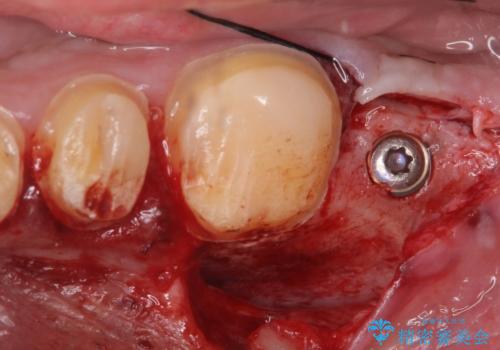

その後、インプラント治療、セラミック治療を行いました。

一度治療するはを全て仮歯に変えて、歯茎を整えてからセラミックを装着しました。

適合の良い被せ物、インプラントが入りました。